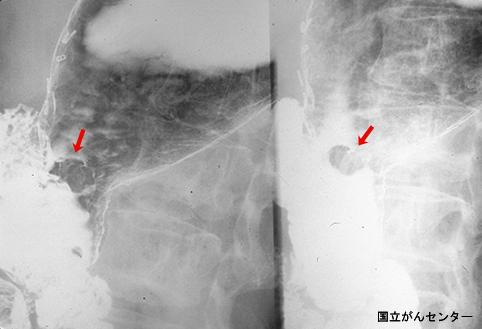

질환(병리주체)의 분류 악성 상피성종양/선암

부위(장기별) 위(부위)/체부

검사방법 X-P

종양의 육안분류 0형(표재형)/I형(I)

종양의 최대경(밀리미터) 15~19

종양의 심달도 m